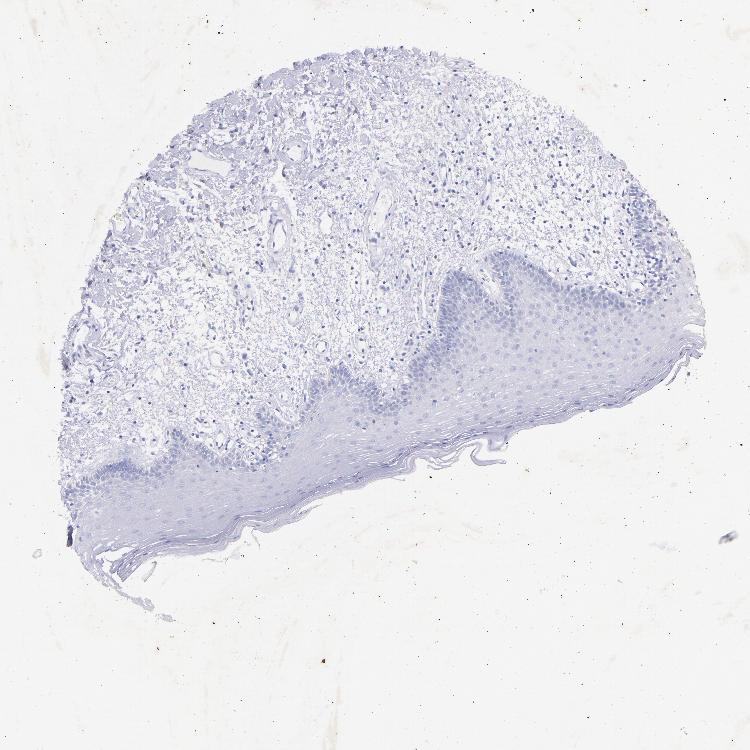

TISSUE PRIMARY DATA ORAL MUCOSA Show tissue menu

ORAL MUCOSA - Antibody stainingi

Antibody staining in the annotated cell types in the current human tissue is reported as not detected, low, medium, or high, based on conventional immunohistochemistry profiling in selected tissues. This score is based on the combination of the staining intensity and fraction of stained cells.

Each image is clickable and will lead to virtual microscopy that enables deeper exploration of all samples and also displays staining intensity scores, fraction scores and subcellular localization as well as patient and tissue information for each sample.

Antibody HPA005993Antibody CAB002580

Squamous epithelial cells Not detectedNot detected